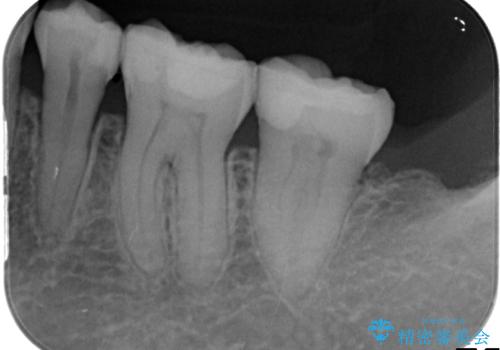

銀歯の下で虫歯の再発 拡大鏡下で行う虫歯の精密治療

- 他院で銀歯の下部に再発した虫歯の存在を指摘され、精密な治療を求めて来院されました。

銀歯下に虫歯が再発すると神経に近くなり、根管治療を必要とする可能性が高まってしまいます。

健全な歯を削らないように拡大鏡下で丁寧に虫歯を除去することで神経を温存し精密なセラミック治療を行うことができました。